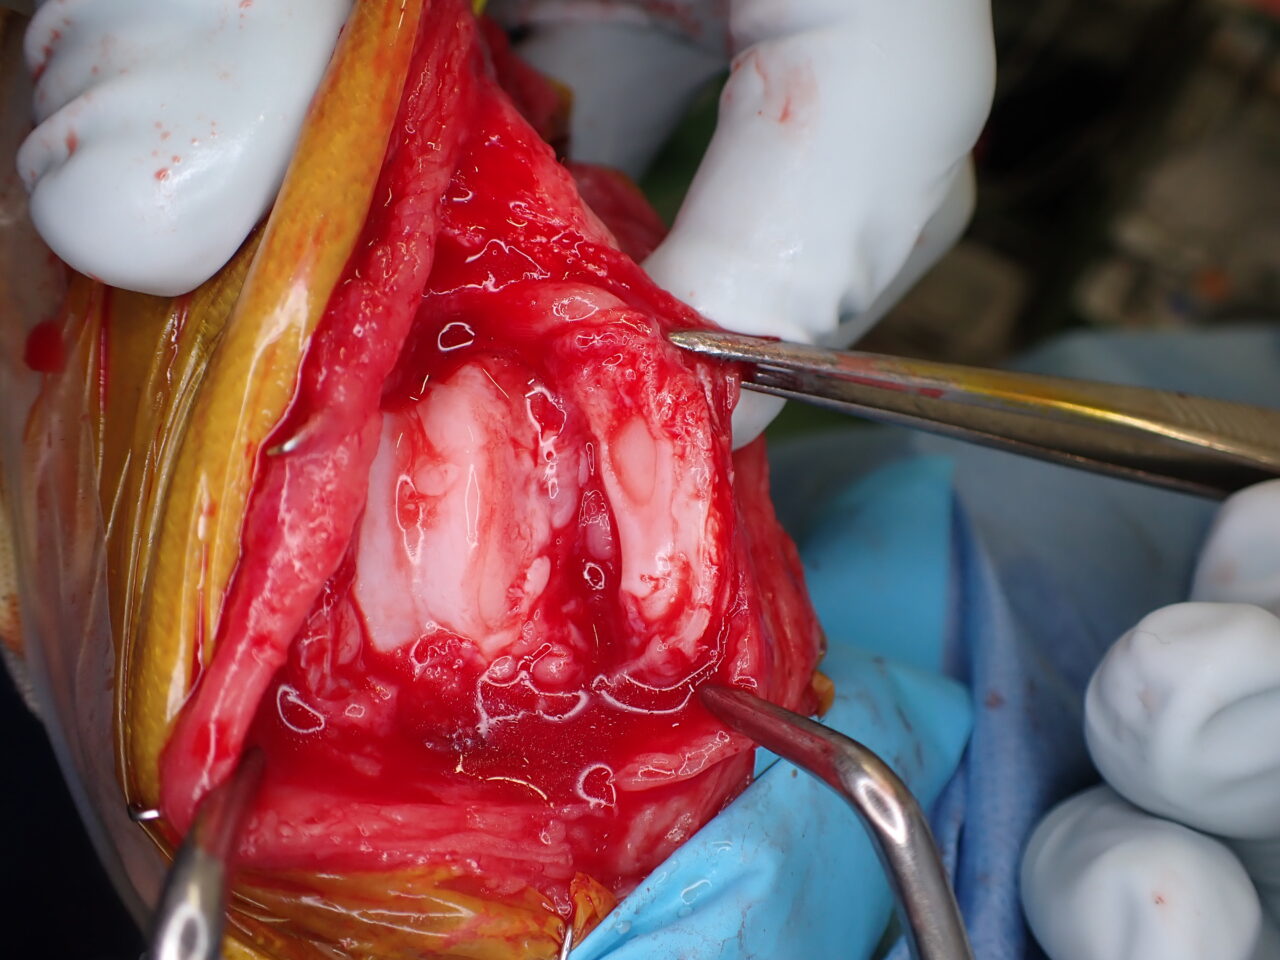

膝蓋骨内方脱臼に伴い慢性の異常な刺激が進行し、骨関節炎を認め関節軟骨はすでに不可逆的な変性を呈しています。多くの外科手術は”整復”を目的としますが、関節炎が進行した関節においては、単なる整復だけでは痛みや機能障害は残り続けます。そこで必要な手技は”再建”です。損傷した関節面をそのまま使うのではなく、人工滑車(PGR)を用いて新たな滑走面(DLC)を構築することで、関節内の異常なストレスを減少させ、除痛と機能回復を図ります。HAコーティングのベースプレートと骨がオッセオ・インテグレーションを起こすまでは安静が必要です。